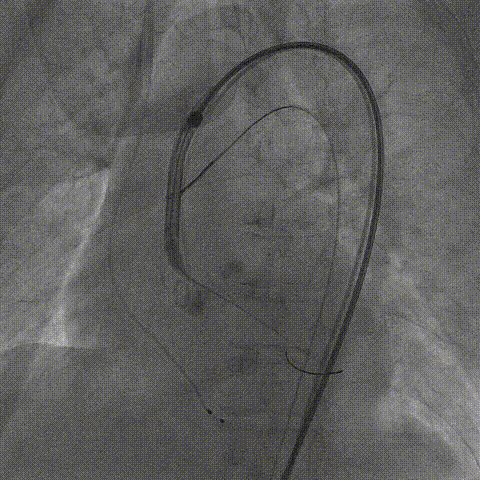

Snare协助输送器跨瓣

瓣膜第一次释放至工作位造影

完全回收后瓣膜第二次释放